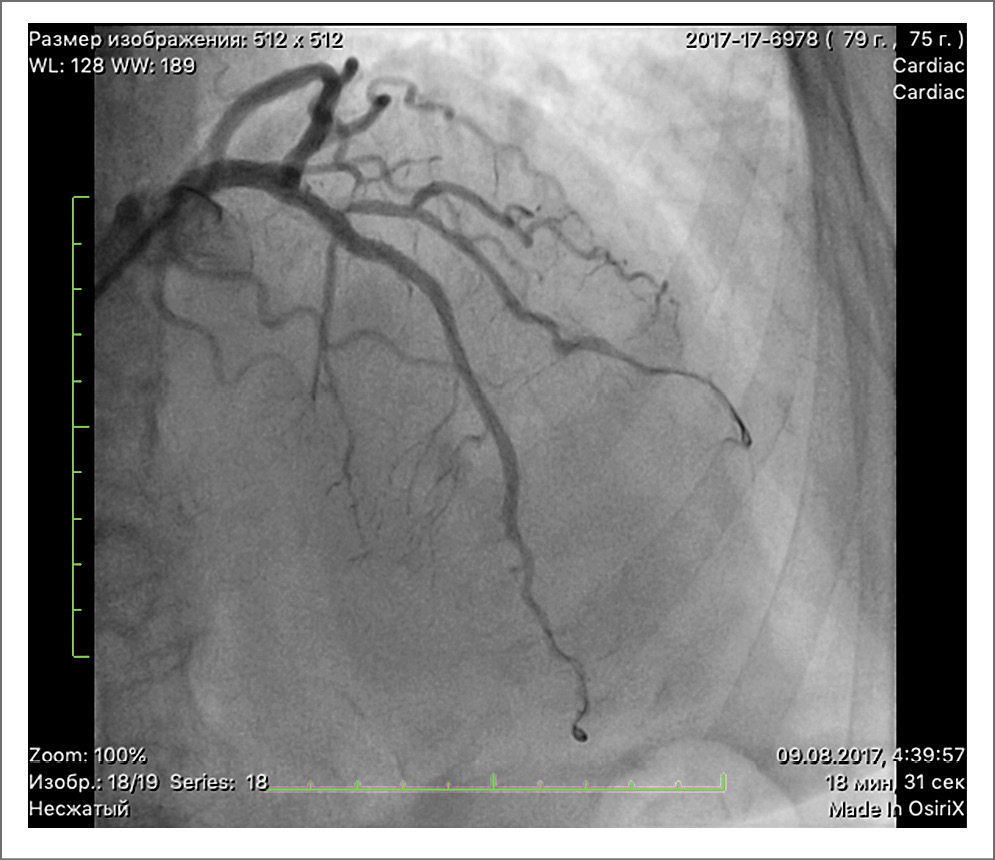

В месте стеноза ПНА установлен стент, однако попытки ввести баллонный катетер в ветвь крупной ДА безуспешны. На серии контрольных ангиографий кровоток в ПНА TIMI 3, в ДА TIMI 2 – в дистальной трети неокклюзирующая диссекция. Остаточный стеноз в месте установки стента в ПНА 0%. На рис. 2 представлена ПНА после ТБКА.

Рис. 2. ПНА после ТБКА